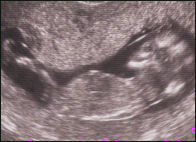

Niskapoimu-ultra kätilön tekemänä. Isikin on tervetullut mukaan, mutta monissa sairaaloissa toivotaan että sisarukset jäisivät kotiin, sillä he saattavat häiritä kätilön keskittymistä. Ultraa ei tarjota kaikissa kunnissa ja se on aina vapaaehtoinen. Vauva muuttuu monille konkreettisemmaksi, kun häntä pääsee "katsomaan". Ultraäänitutkimuksilla on kuitenkin monta tavoitetta. Mittaamalla sikiön koko voidaan paremmin arvoida raskauden kestoa, nähdään montako sikiöitä on ja mihin istukka on kiinnittynyt. Lisäksi rakenteellisia kehityshäiriöitä seulotaan - eräs olennainen on kromosomipoikkeamasta johtuva Downin oireyhtymä.

Sikiön pituus on n. 10 cm, pää on iso ja vartalo vielä hyvin hintelä. Äidin paino noussut parisen kiloa. |